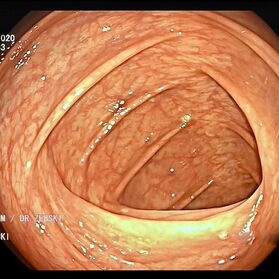

Die Darmspiegelung ist der uneingeschränkte Goldstandard für die Diagnostik und Vorsorge sämtlicher Erkrankungen des Dickdarms und des untersten Dünndarms. Die hochauflösende Bildqualität (High Definition) unserer modernen Videokoloskope ermöglicht eine zuverlässige Einordnung nahezu sämtlicher entzündlicher oder geschwulstiger Veränderungen der Dickdarmschleimhaut.